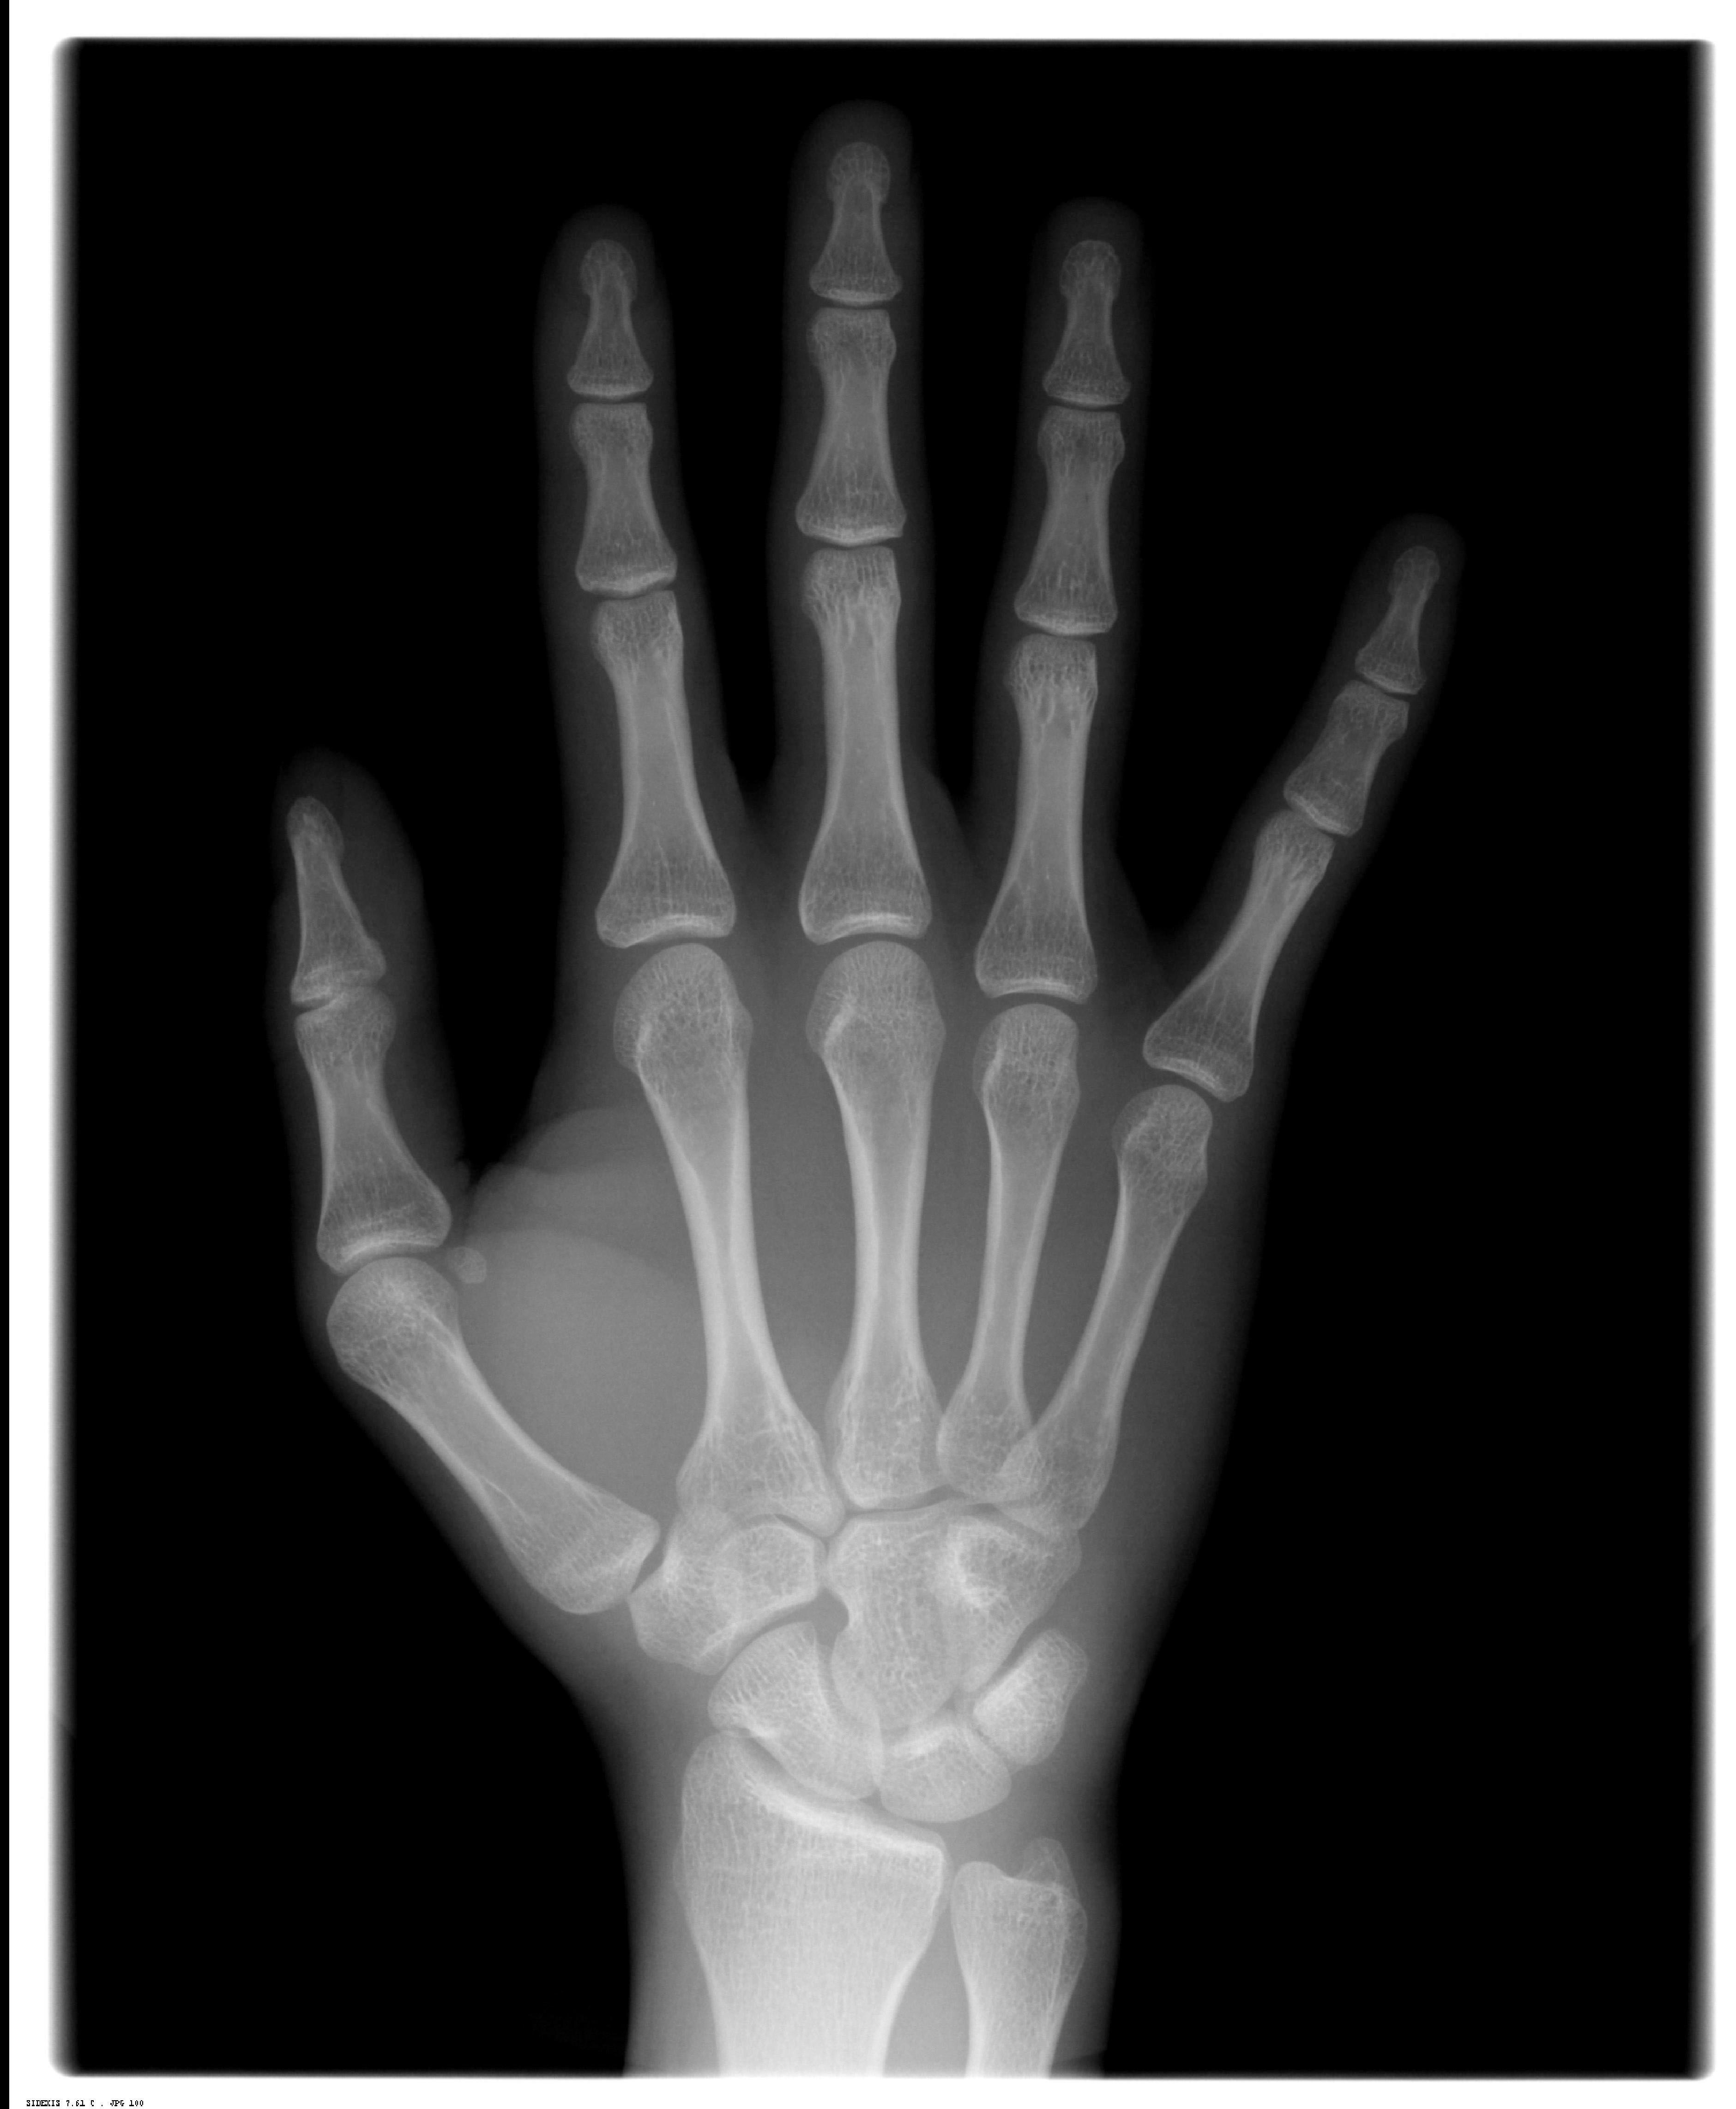

Radiografia Carpal (Mão e punho)

Técnica Radiográfica Extra bucal, executada na região de mão e punho que auxilia o Cirurgião-Dentista a avaliar o crescimento ósseo do paciente com relação à idade cronológica do mesmo.